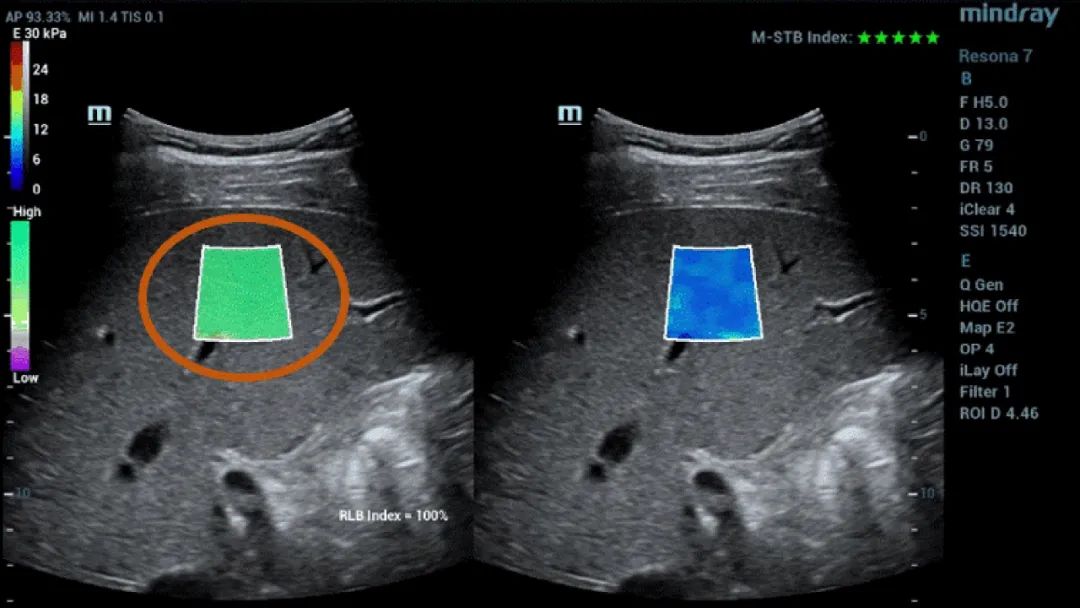

Afbeelding 1 (vervolgd): (e) Beelden verkregen met 2D SWE (STE; Mindray, Shenzhen, China). Er worden twee kwaliteitscriteria gegeven: de index voor bewegingsstabiliteit (M-STB), die wordt aangeduid met sterretjes (de hoogste stabiliteit wordt aangeduid met vijf groene sterretjes), en het betrouwbaarheidsraster (RLB: reliability), dat van paars naar groen gaat, waarbij groen de hoogste betrouwbaarheid aangeeft. De sterretjes zijn een indicator van beweging tijdens de verwerving. Bij minder dan vier sterretjes is er aanzienlijke beweging tijdens de verwerving en dat frame mag niet worden gebruikt voor de meting van de leverstijfheid. (f) Verkregen beelden.

Daarnaast biedt Mindray's Sound Touch Elastography (STE) krachtige kwaliteits- of betrouwbaarheidsfactoren, waaronder de M-STB-index (bewegingsstabiliteit), het betrouwbaarheidsraster (RLB), de betrouwbaarheidsindex (RLB), enz. voor metingen verkregen met 2D-Shear Wave-elastografie. Dit helpt operatoren de standaarden voor beeldverwerving te bevestigen.

Wat is het M-STB-weergave/de M-RLB-index ?

Het RLB-raster geeft de betrouwbaarheid van STE-beelden aan en gaat van paars naar groen, waarbij groen de hoogste betrouwbaarheid aangeeft. Wanneer de RLB-index ≧90% is, is het beeld betrouwbaar.